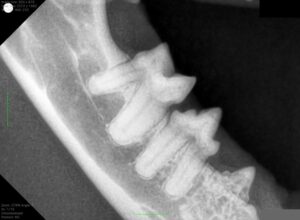

↑歯科レントゲンの画像の例です。画像の左側2本の歯は比較的良い状態が保たれています。